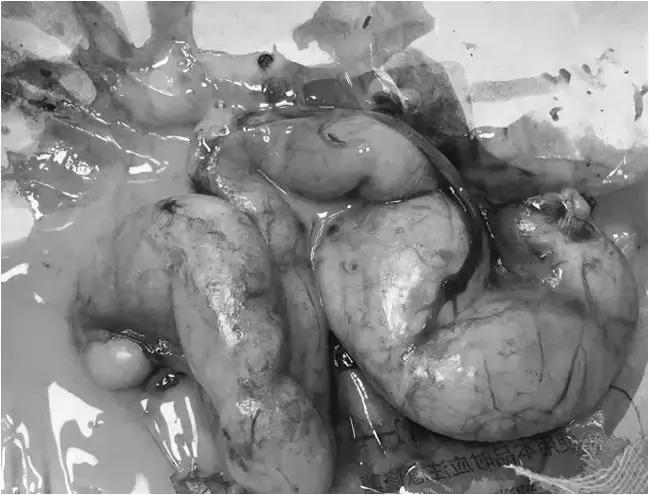

除此之外还进行外科手术

将已感染的卵巢和子宫一并切除

虽已经历3个多月的病痛折磨

但猫咪现已完全恢复健康!